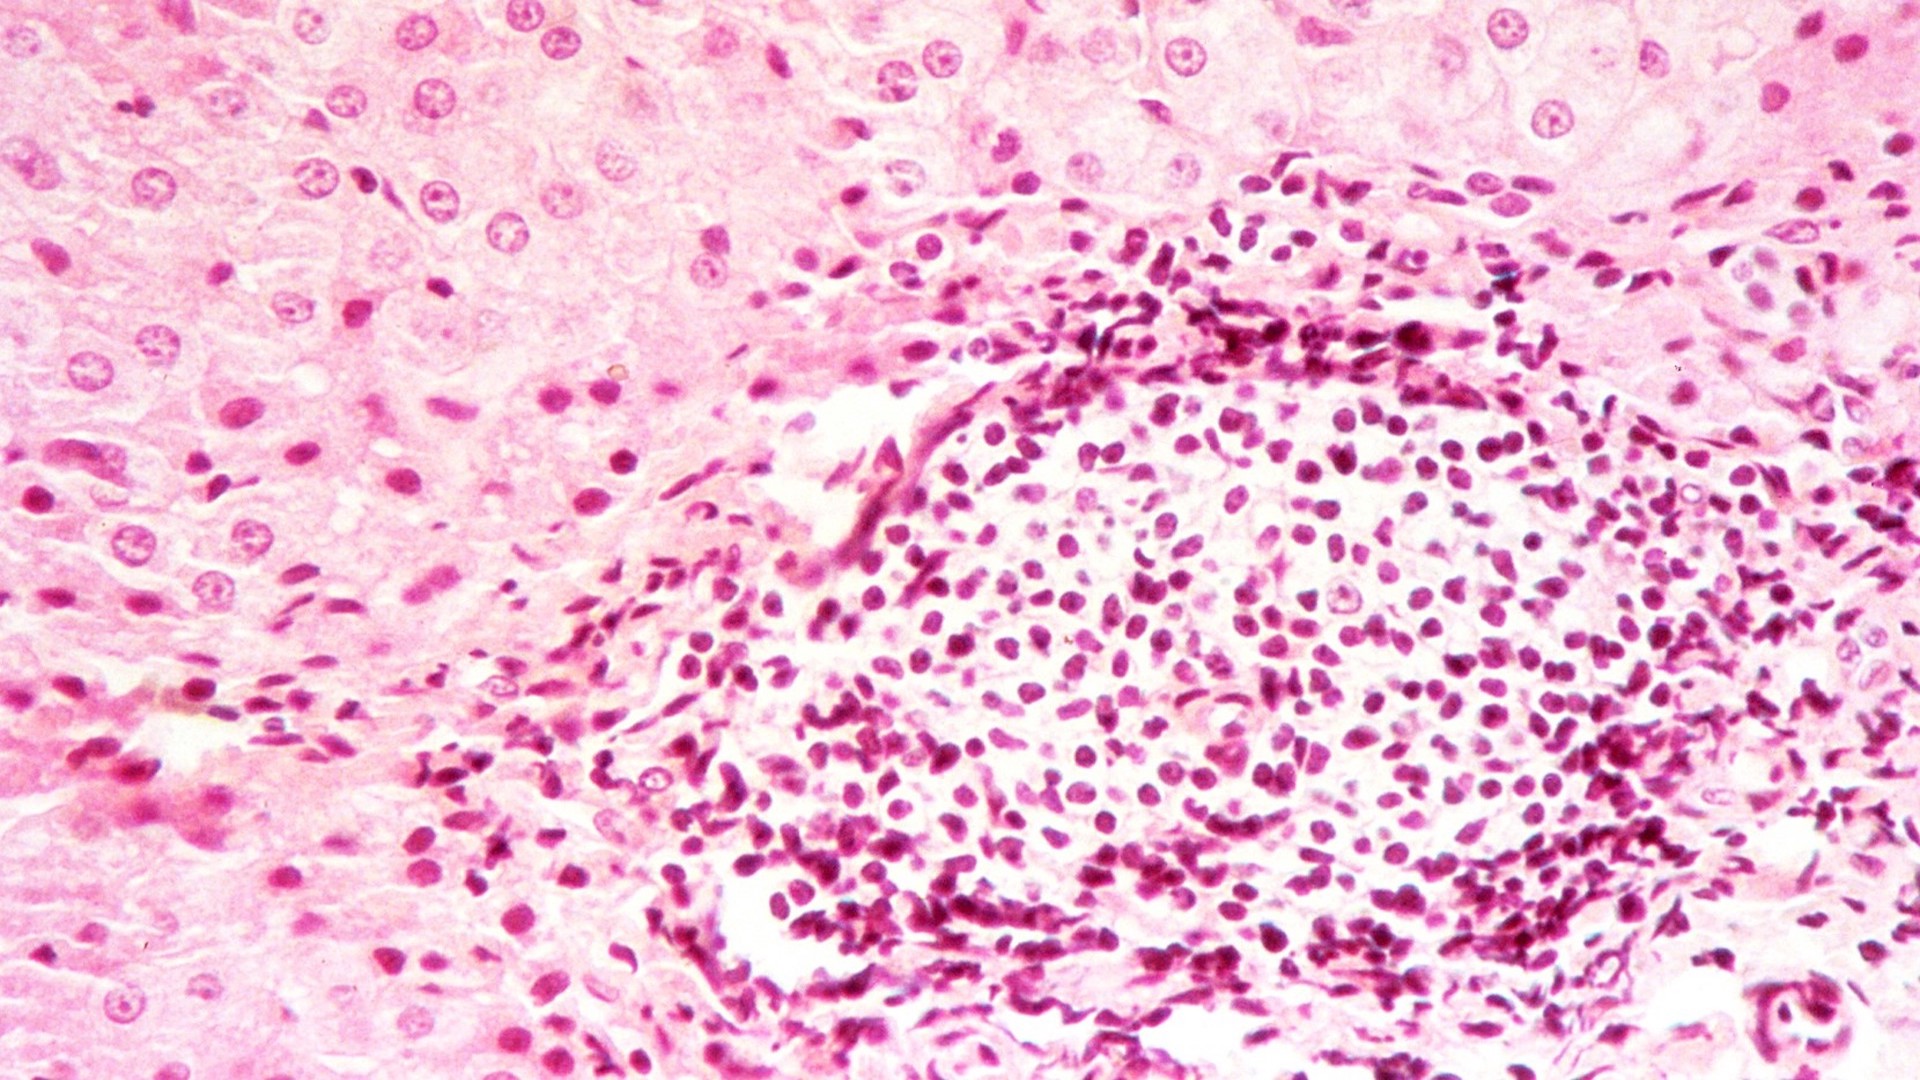

Epidémiologie et Physiopathologie des Virus Oncogènes